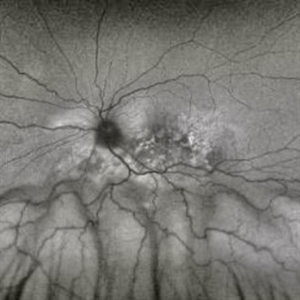

Exudative Retinal Detachment

Exudative Retinal Detachment

Aug 6 2025 by Aditya S Kelkar, MS, FRCS, FASRS,FRCOphth

Fundus auto-fluorescence of a 41 year old female depicting retinal pigment epitheliopathy and exudative retinal detachment in case of ocular metastasis secondary to breast carcinoma.

Photographer: Dr.Rabia Naaz, National Institute of ophthalmology, Pune

Imaging device: OPTOS DAYTONA

Condition/keywords: Exudative retinal detachment, Retinal pigment epitheliopathy